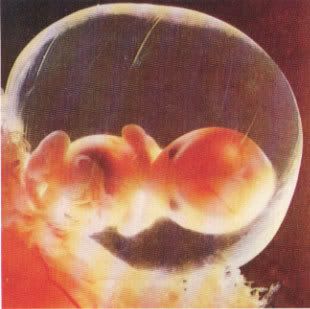

La gravidanza procede bene ed ormai siamo veramente agli sgoccioli. Girovagando per internet guardate cos'ho trovato....incredibile....è veramente il MIRACOLO DELLA VITA

La gravidanza procede bene ed ormai siamo veramente agli sgoccioli. Girovagando per internet guardate cos'ho trovato....incredibile....è veramente il MIRACOLO DELLA VITA